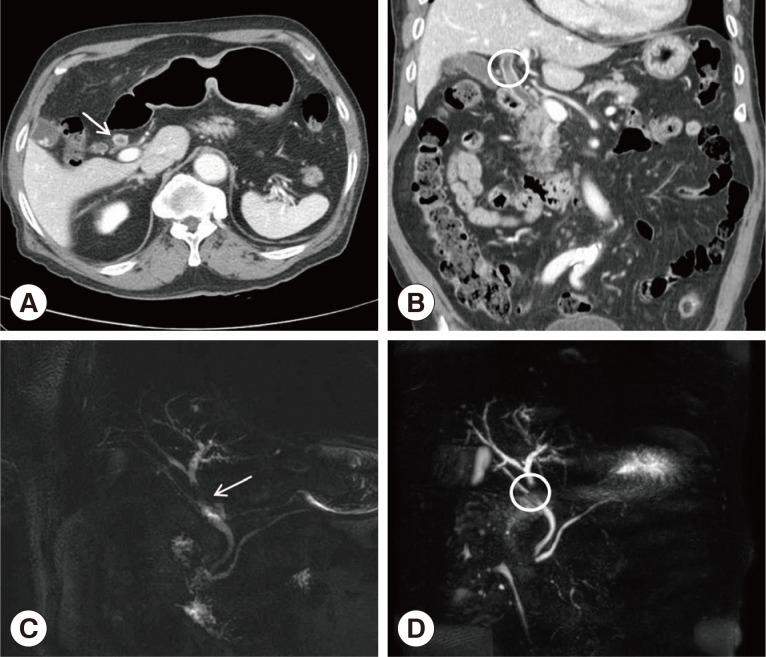

An 87-year-old man who had postprandial abdominal pain and discomfort for several months was referred to us for evaluation. CT revealed intraductal soft tissue in the CBD without definite evidence of ductal obstruction and segmental bile duct wall thickening, which suggested a bile duct cancer (Fig. 1A, B). For differential diagnosis, magnetic retrograde cholangiopancreatography (MRCP) was performed, which showed segmental wall thickening with papillary filling defect at the CBD, with minimal upstream duct dilatation (Fig. 1C, D). The laboratory findings were within normal limits, except for peripheral eosinophilia (1,091 eosinophils per mm3, 13.3% of the total WBC). To obtain tissue for pathological diagnosis, ERCP was done which demonstrated a small filling defect of the mid-CBD (Fig. 2A). After endoscopic sphincterotomy, 2 living leaf-like parasites were removed from the CBD using a basket (Fig. 2B). At that time, he was diagnosed presumptively as Clonorchis sinensis infection. Thus, he took praziquantel at 3 doses of 25 mg/kg (total 75 mg/kg) for 1 day. However, consequent detailed morphological examinations revealed that the parasites recovered were not C. sinensis but F. hepatica. The adult flukes (Fig. 2C) were 2.6×1.2 cm in average size (n=2). The eggs (Fig. 2D) recovered from the uterus of a worm were 135-145×65-80 µm in size (n=5). These morphological findings were compatible with those of F. hepatica [5].

In the present case, we performed stool examinations but there were no eggs probably due that the patient was in an acute phase of infection. Because the biliary phase of F. hepatica infection is usually asymptomatic, our patient was a rare case who presented with biliary obstruction [9]. The CT images are sometimes confused with malignancy or stones, similar to our case [10]. We made a tentative diagnosis as an intraductal tumor or radiolucent stone, even after CT and MRCP. In Korea, there were some cases of fascioliasis which mimicked cholangiocarcinoma [11]. Unlike intraductal cholangiocarcinoma, our patient had normal liver functions even though an intraductal mass with mild biliary obstruction was seen on radiological examinations.